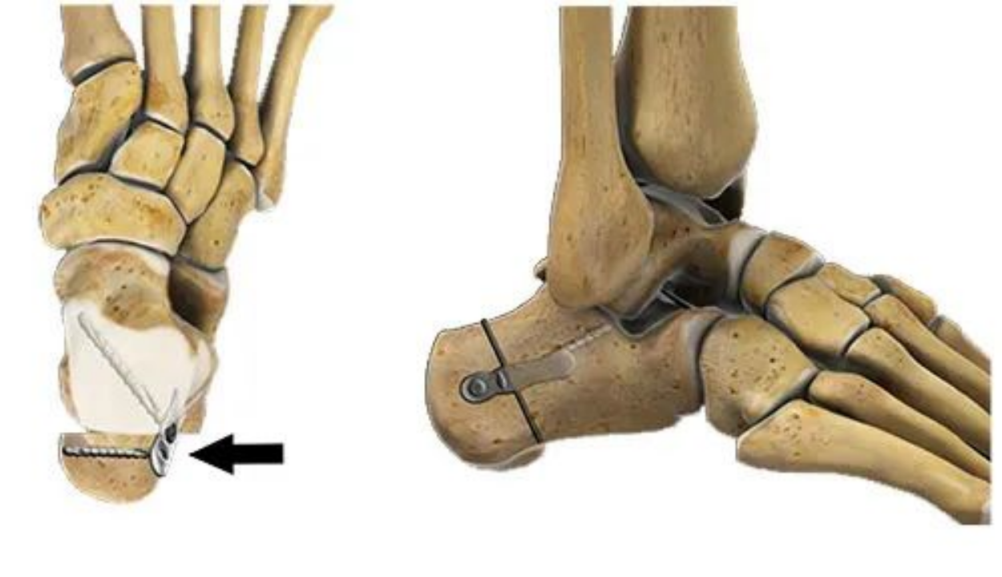

很快X光片结果出来后,和医生的初步诊断一致,最终诊断为“先天性平足”。此前,因孩子学业问题一直未能得到系统矫正,以至于现在已经到了疼痛无法忍受的地步,医生的建议是进行手术治疗。起初,孩子家长有些犹豫,但经过医生细致耐心的沟通后,也为了孩子的以后着想,很快决定接受手术。手术采用微创的方法在双足内植入距下制动器,来纠正畸形。手术顺利,孩子也已经在恢复阶段。

对于8-14岁的有疼痛症状,或经过保守治疗仍存在疼痛,建议进行手术治疗,即微创植入距下制动器治疗;对于畸形非常严重的平足,单纯通过距下制动器可能无法完全纠正畸形,则要在植入制动器的基础上辅助截骨增强矫形能力。